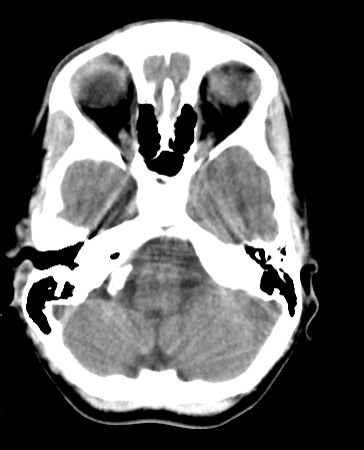

Identify the following structures in the head CT. To view the location of the structure in the image click on the label at the left and an arrow will point to the structure in the image.

Cerebellar Tonsil

External Auditory Canal

Mastoid Air Cells

Sella Turcica

Sphenoid Sinus